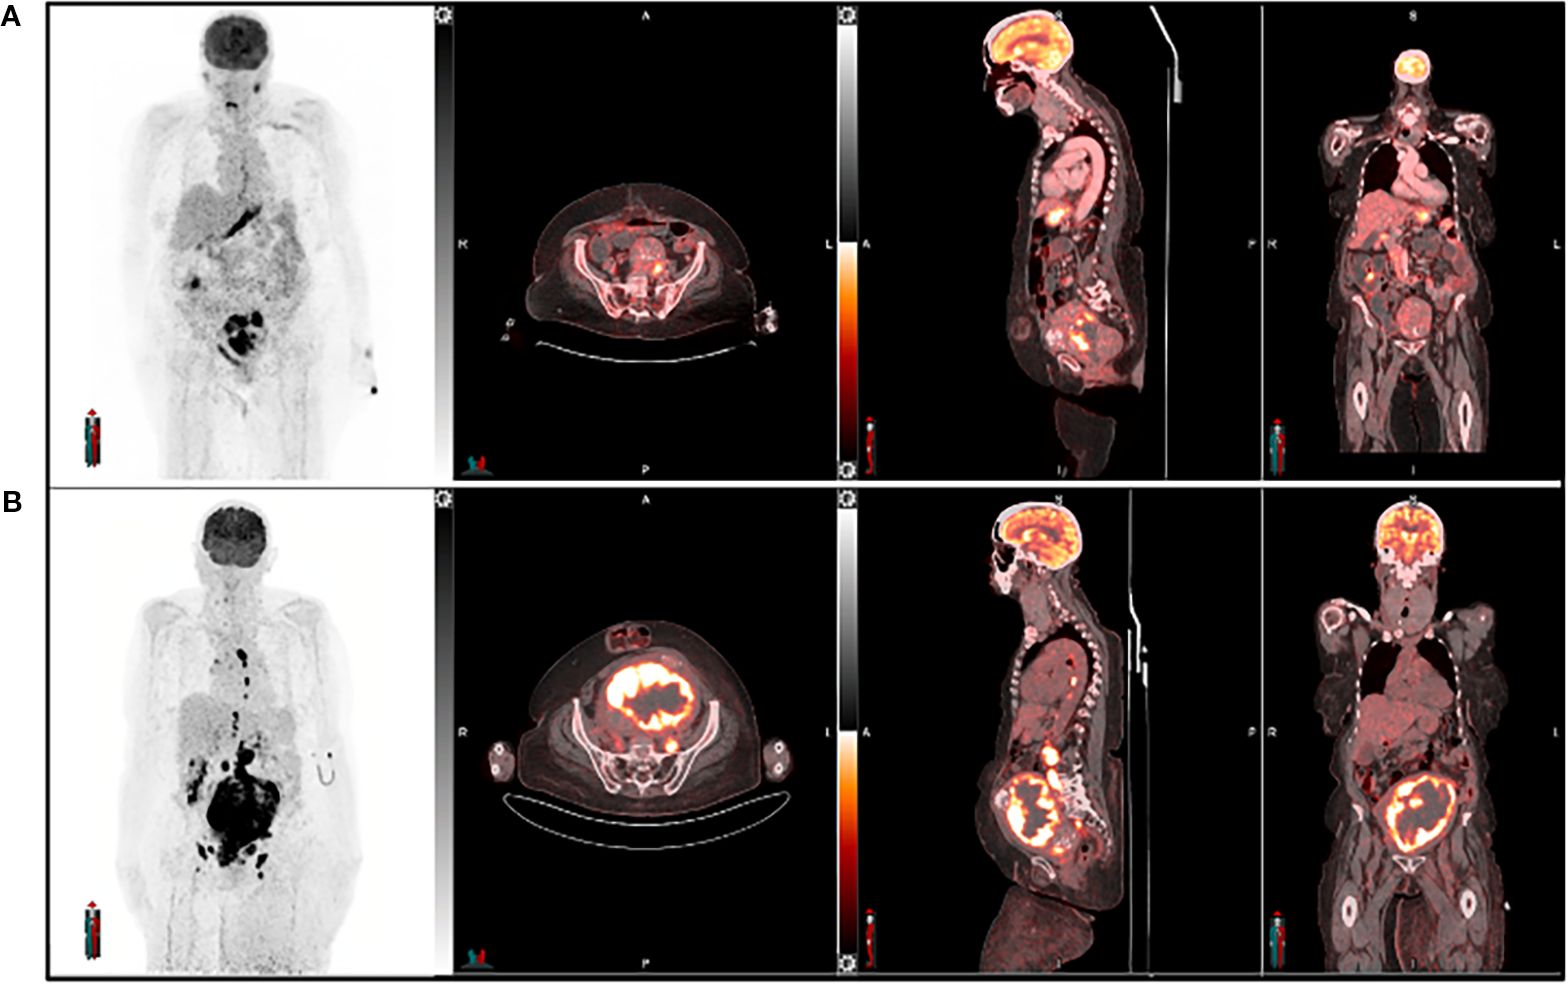

Keywords: Nrf2 activation, Oxidative Stress, tumor progression, Therapyresistance, gynecological cancers, Targeted inhibitors, PET imaging, Personalizedtreatment